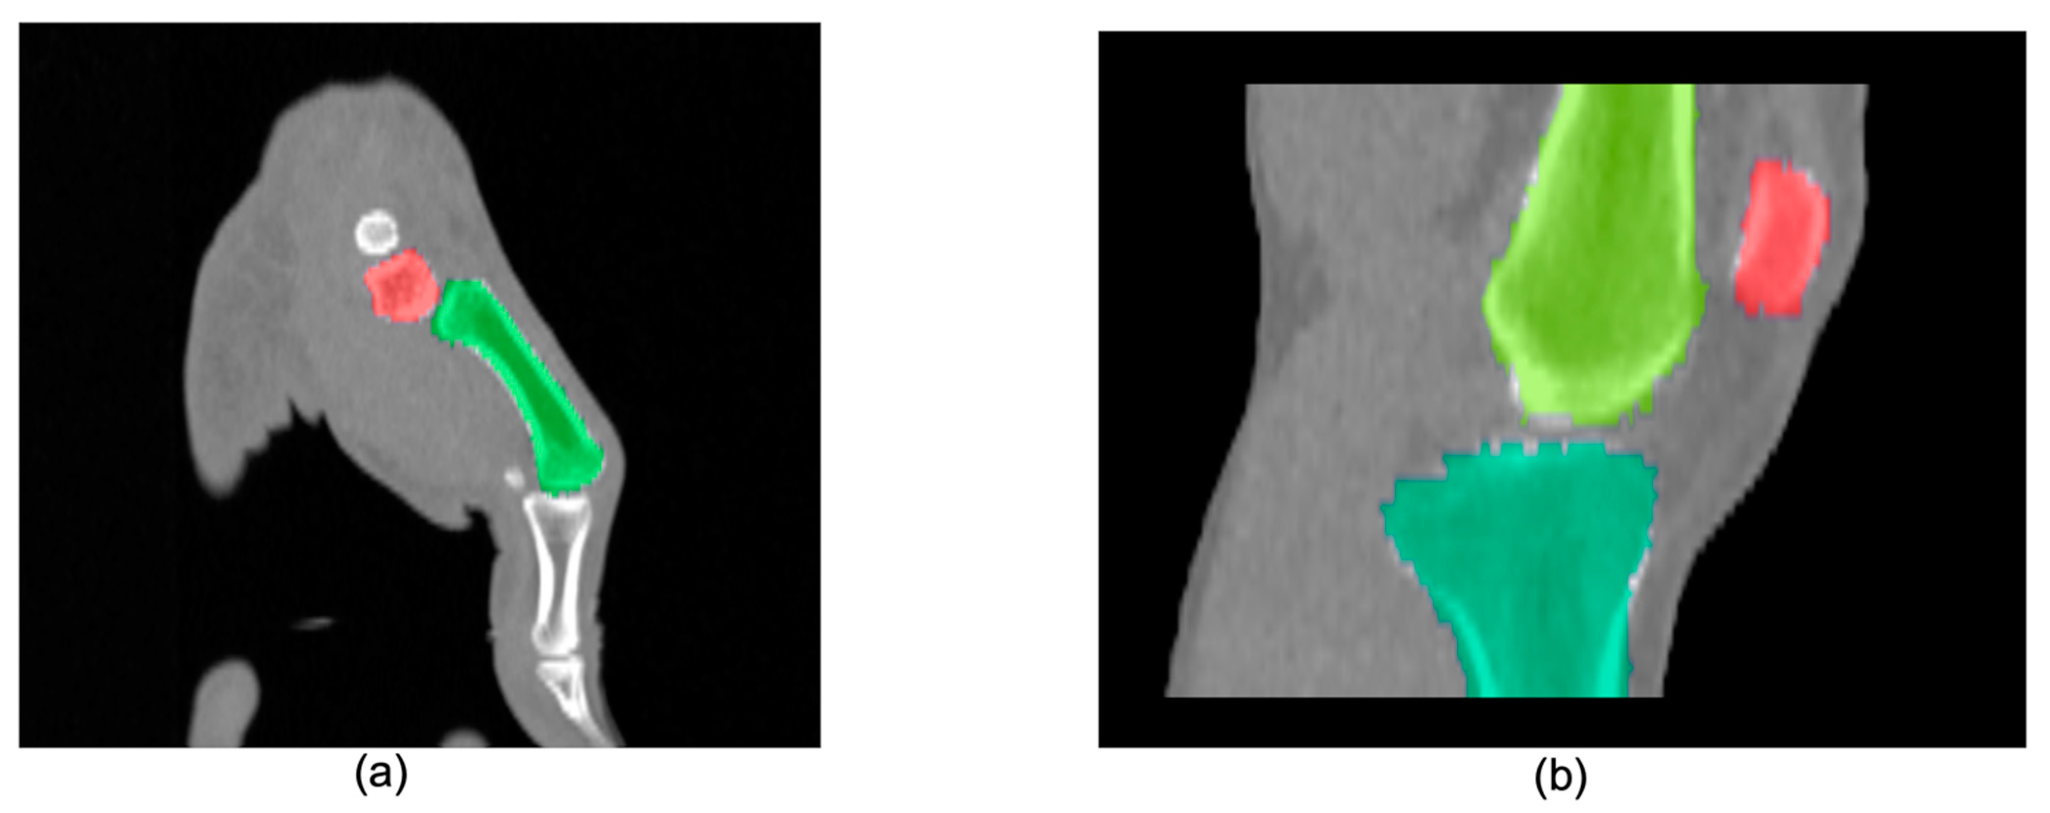

3.1. Multi-Atlas Segmentation